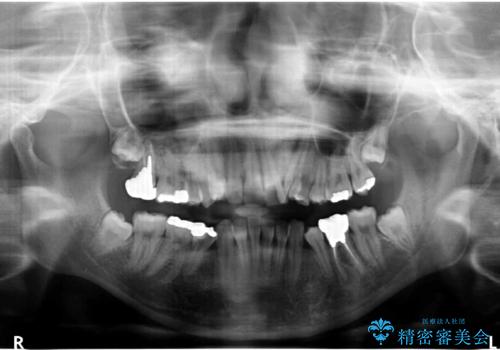

小さいころ下の小臼歯を2本抜いたとのことでした。

上の歯を2本抜歯して矯正しています。

また、右上の7番(一番後ろの歯)の状態が悪く、根尖病変がありました。根の治療をする選択肢もありましたが、歯質も薄く、予算的にも治療が難しかったため、抜歯して親知らずを並べています。

左下6番(後ろから2番目の歯)も状態が悪かったため抜歯してブリッジにしています。

矯正治療をしたことで根の向きが治り、神経を取らずにブリッジにすることができました。